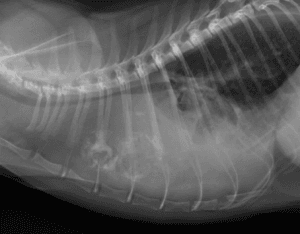

犬の鼻腔内腫瘍

犬の鼻腔内腫瘍は、上皮性腫瘍(腺癌、扁平上皮癌、未分化癌など)が最も多くを占め、残りの多くは非上皮性腫瘍(線維肉腫、軟骨肉腫、骨肉腫、未分化肉腫など)とされています。腫瘍の種類にかかわらず、臨床症状は共通しており、初期に […]